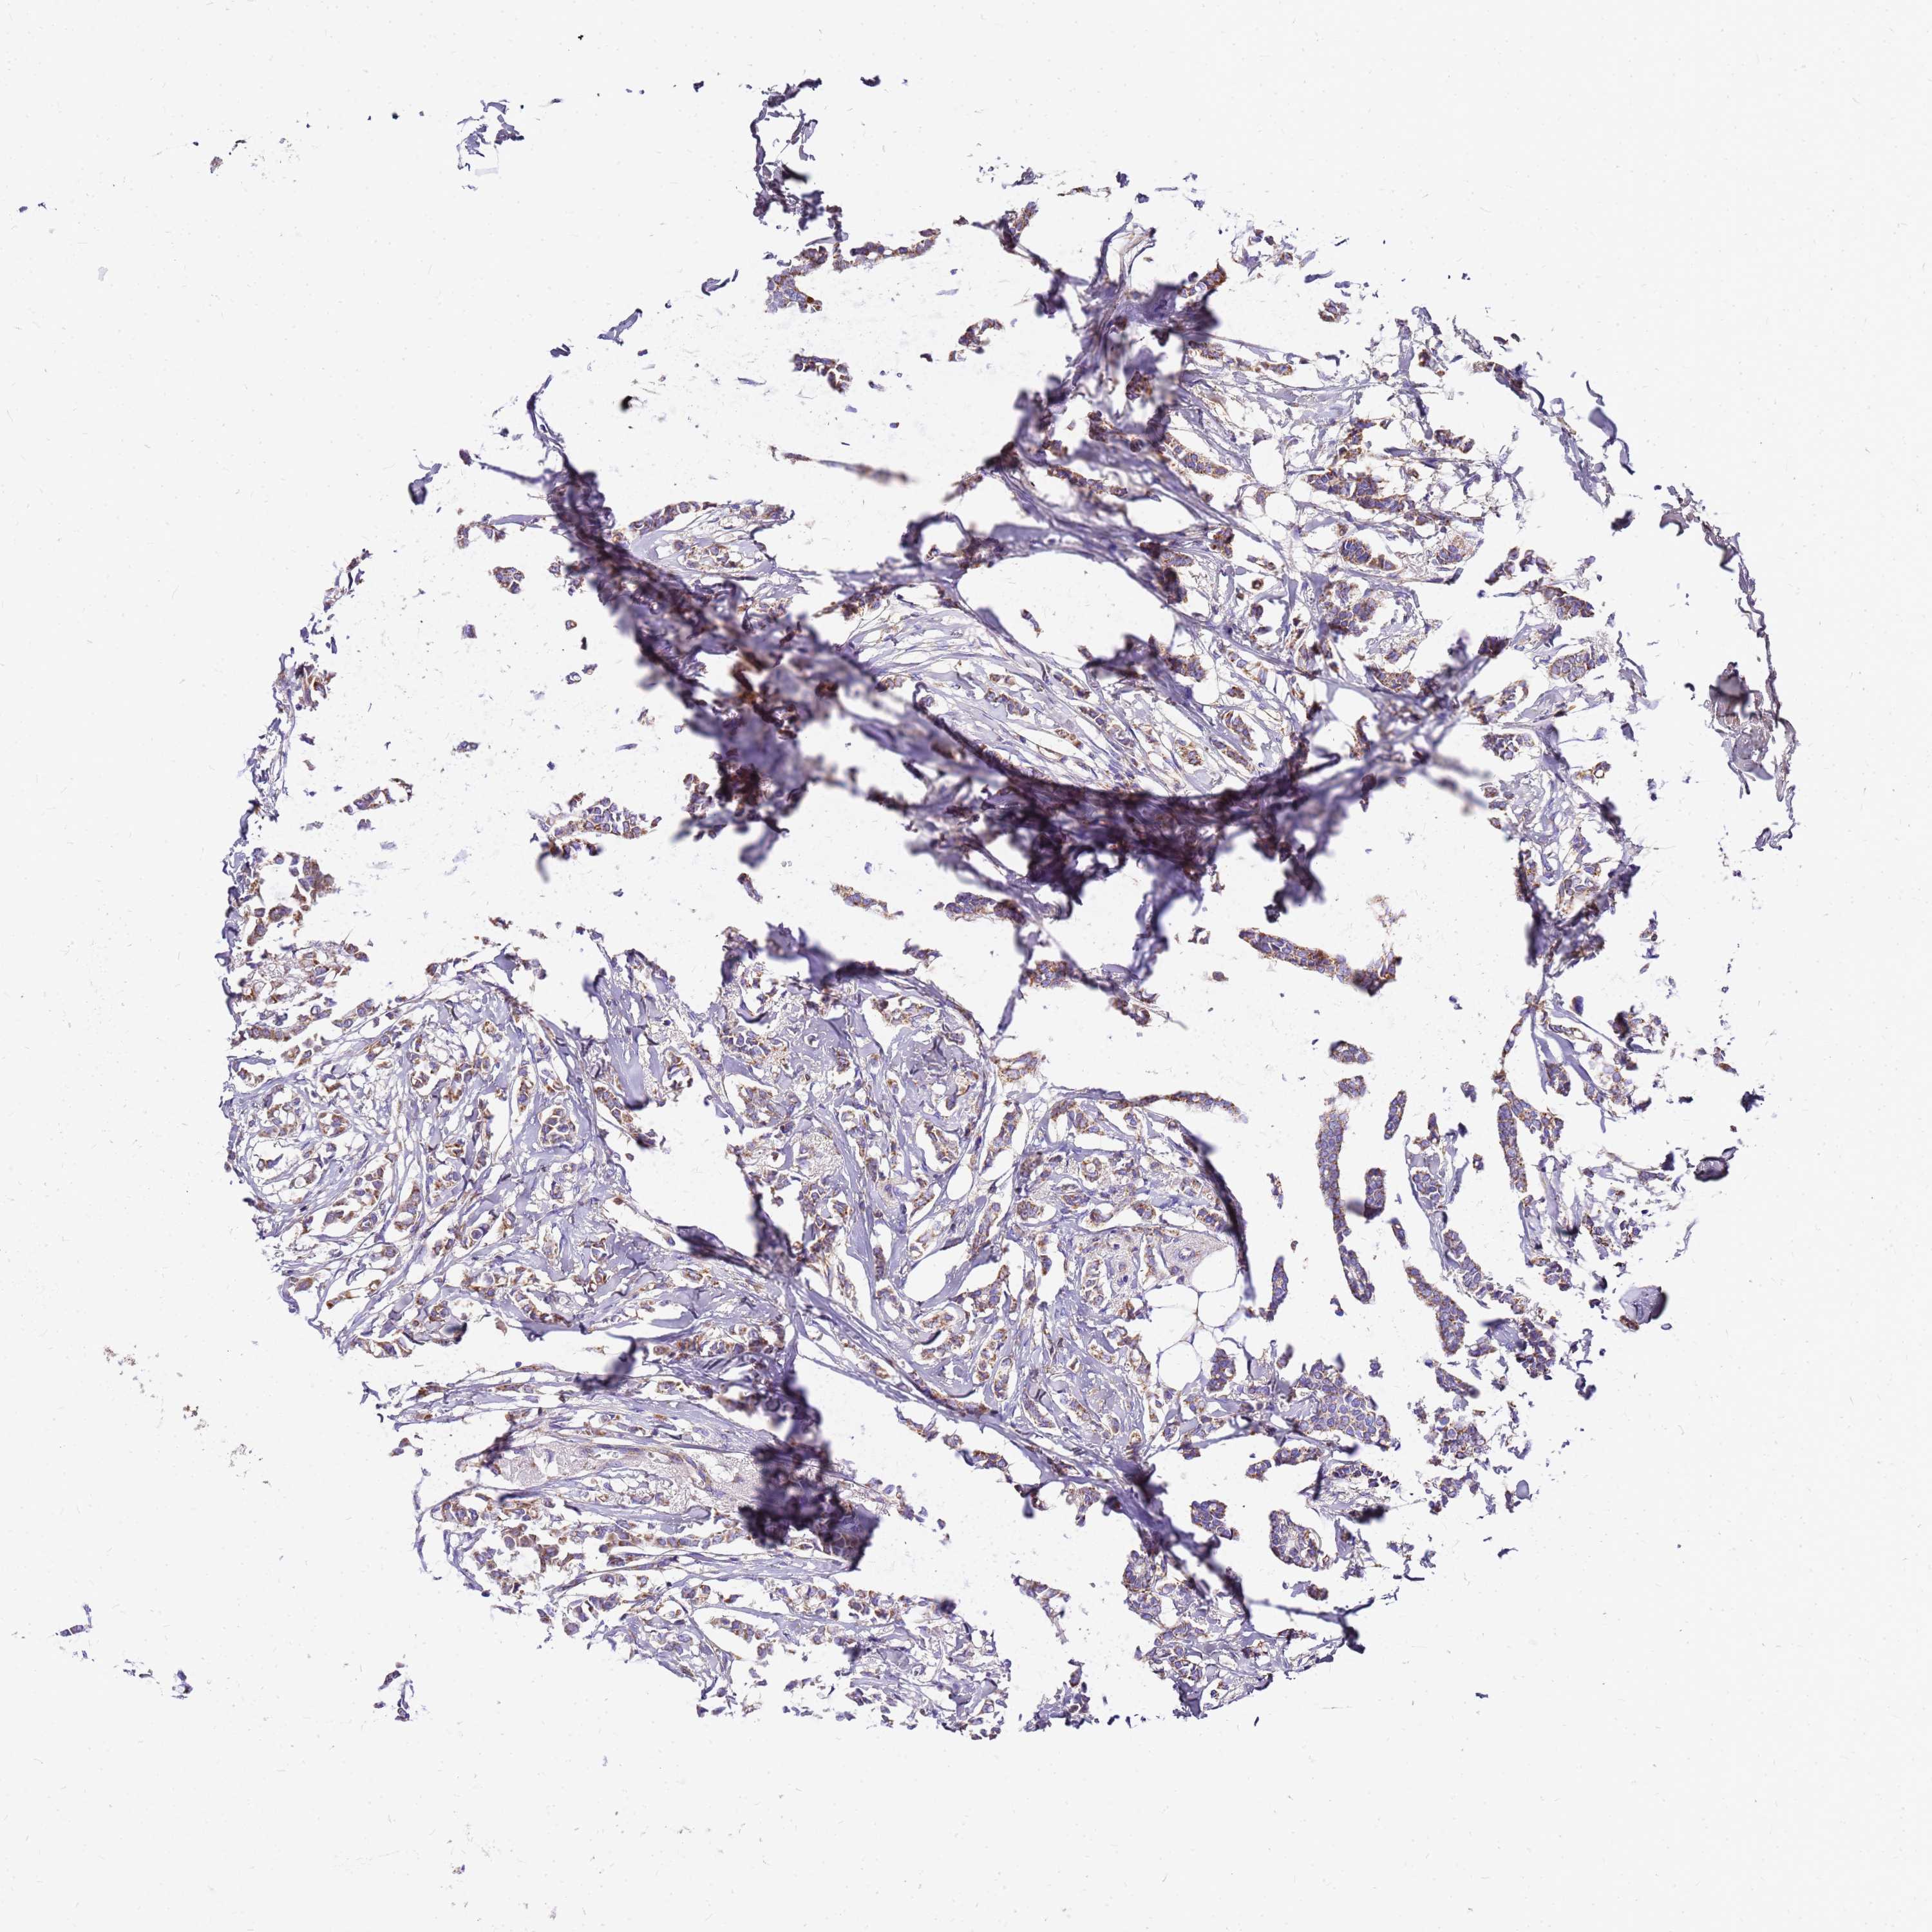

CANCER BREAST CANCER Show tissue menu

BRCA TCGA BRCA VALIDATION PROTEIN EXPRESSION